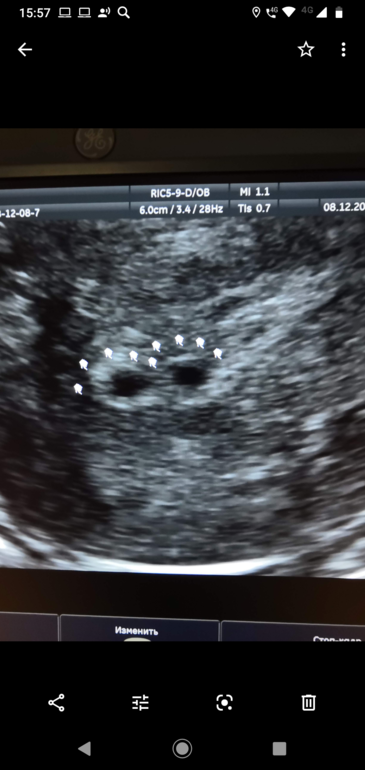

У меня так выглядело.

Помогла гистероскопия